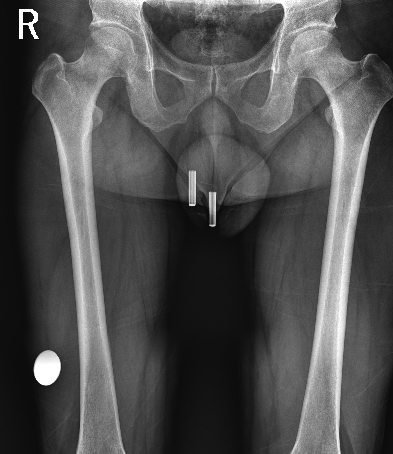

平板探测器

超大尺寸

超范围